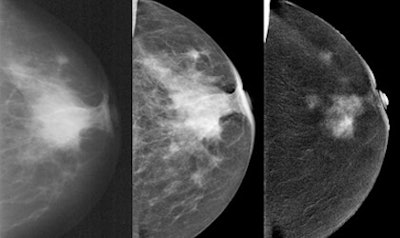

The study was approved by the German governmental Health Authorities and Ethics Committee, and included 68 patients with biopsy-proven breast cancer. Contrast-enhanced digital mammography was performed as a bilateral mammogram (Senographe DS, GE Healthcare), starting two minutes after injection of 1.5 mL/kg of an iodinated contrast agent (300 mg/mL) with a flow of 3 mL/sec. Contrast-enhanced digital mammography and mammography images were interpreted by three blinded independent radiologists with an interval of four weeks for memory washout.

The researchers found 23 false negatives in mammography. There were three false negatives in the combination (mammography plus contrast-enhanced mammography) and two false negatives in contrast-enhanced mammography alone. Sensitivity was 87.6 % for mammography, 97.4% for contrast-enhanced mammography, and 92.3% for the combination.

"Contrast-enhanced digital mammography alone showed equal detection and sensitivity for the index cancer than the combination with mammo," Fallenberg concluded. "It is superior to mammo alone in lesion detection, and there was no significant difference in size evaluation between all the three modalities. So I would say in symptomatic patients we can start with contrast-enhanced mammography alone upfront and save 50% of the radiation dose."